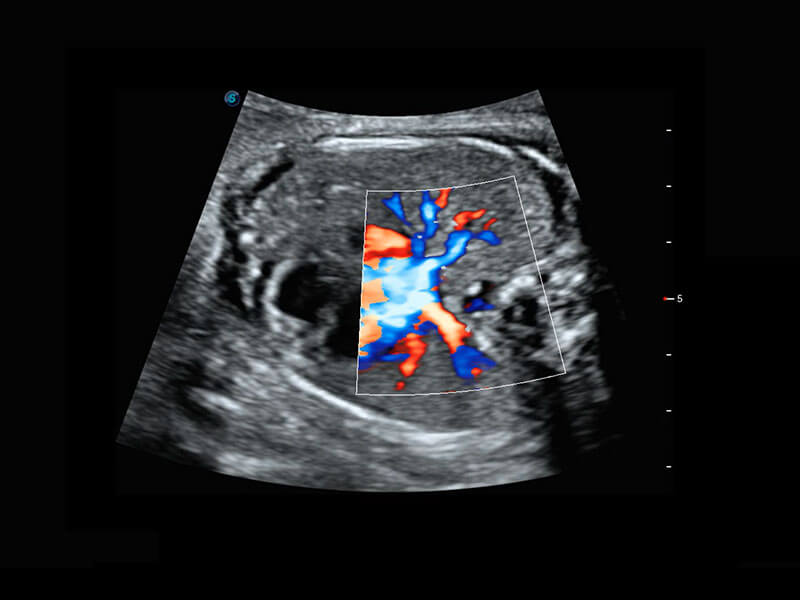

P60优异的图像质量搭载专科探头,在妇科基础疾病的诊断、卵泡生长的监测、输卵管通畅情况的判别等方面为您提供生殖应用方案。

腔内妇科-卵巢